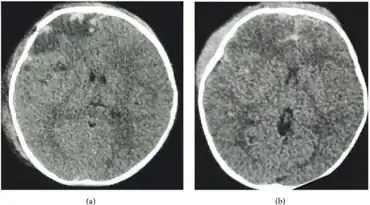

| Cerebral salt wasting syndrome following head injury in a child-image shows fracture of right frontal bone and subdural hematoma and extradural hematoma with contusion and subarachnoid hemorrhage | |